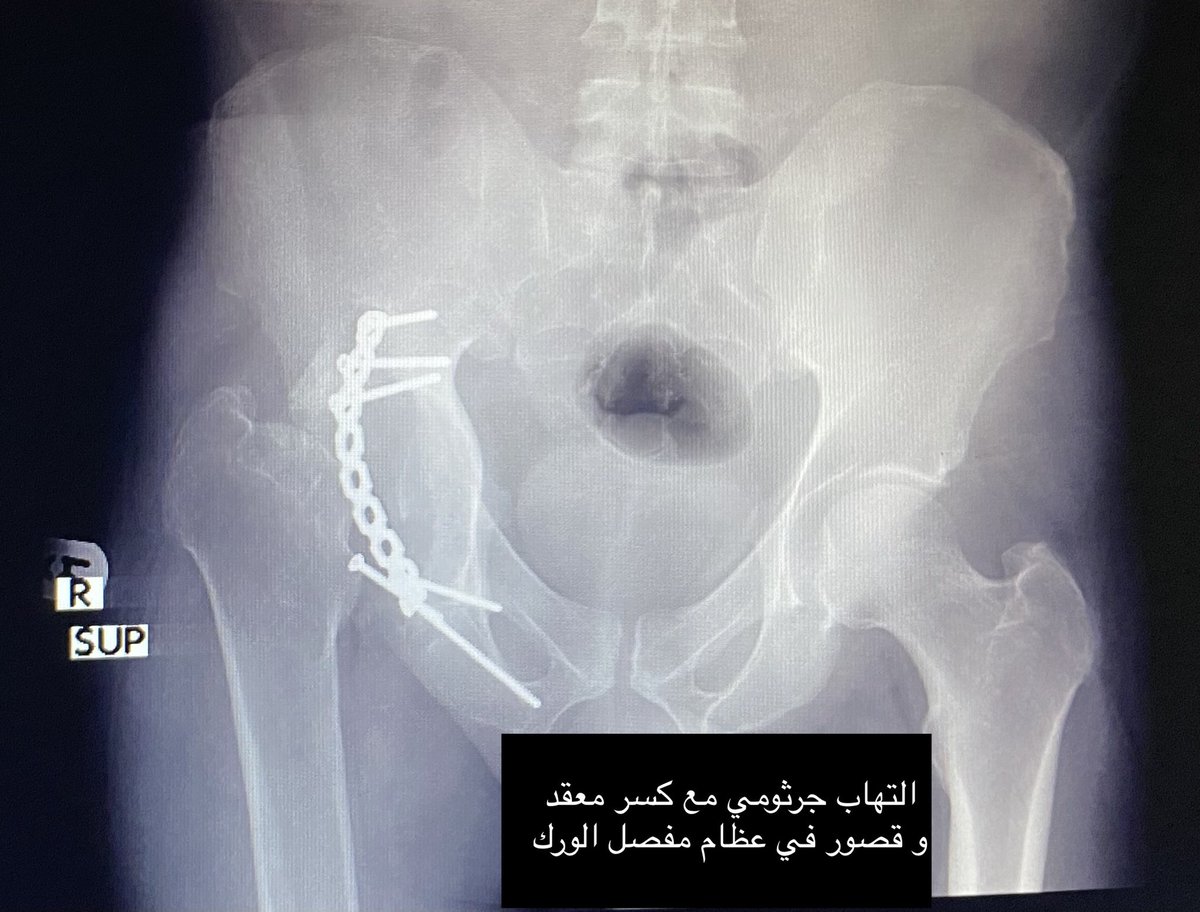

⛔️التهاب جرثومي😢

الحاجه: ازاله الالتهاب و المعدن، تنظيف الكسر واستبدال المفصل المعطوب بمفصل موقت "PROSTALAC" مخصص للمريض حتى ينهي المضاد الحيوي دورته العلاجيه و يقضي على البكتيريا الساكنه في عظم المريض منذ خمس سنين..

الابتكار: استخدام مواد اساسيه، لتشكيل مفصل صناعي مؤقت ومناسب لحجم المريض💫💫

🅰️: صناعه قالب مخصص للمريض باستخدام البولي ميثيل ميثاكريلات الطبي

🅱️: صب اسمنت طبي مطعم بالمضاد الحيوي الفاعل ضد جمله عامه من الجراثيم